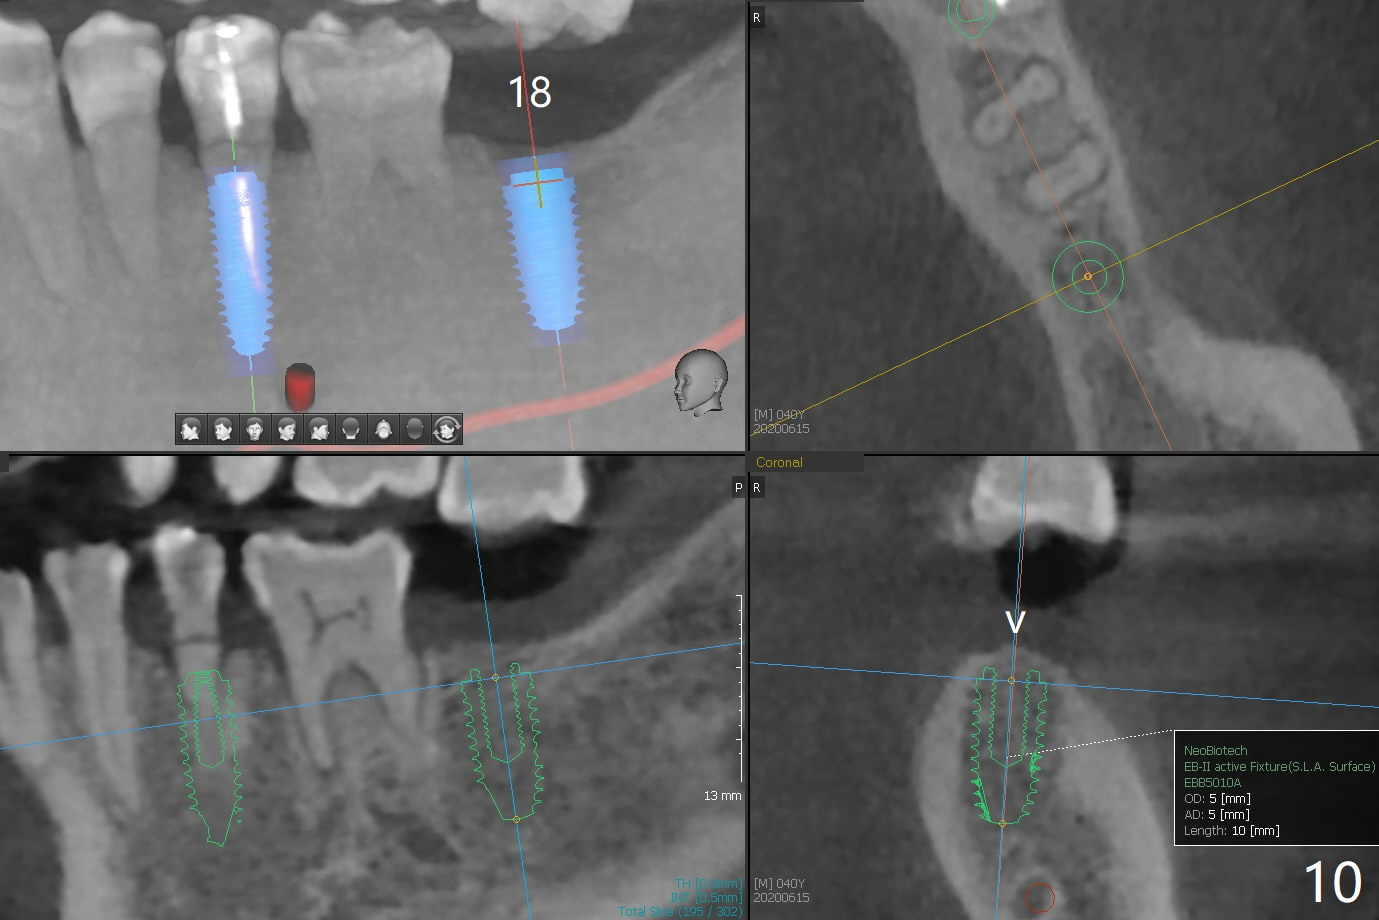

A 40-year-old man with #18 missing and #31 residual roots just fractures the tooth #20 (Fig.1). After discussion, he agrees to have implants at #18 and 20 first. To prevent buccal drifting of osteotomy and implant at #20, the implant will be placed lingual, but it does not contact the lingual plate (Fig.2-4). Traditionally, the whole tooth needs to be extracted (Fig.5,6) before initial osteotomy (Fig.7 red). The latter has tendency to drift buccal because of the lingual slope (Fig.7 arrow). To prevent the drifting, the crown of the tooth is removed (Fig.8). A guide is fabricated with 12 mm offset so that after bone trimmer (Fig.9 pink), the following drills have more contact with metal sleeve. Furthermore the drills will have less chance of buccal shifting because of the presence of the root.

To prevent buccal or lingual drill drifting over the pointed ridge at #18 (Fig.10 v), flap will be raised to make sure the ridge top is flattened before osteotomy.